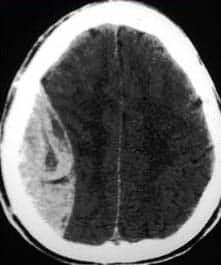

Fig 1.1 - CT scan of a massive extradural haematoma

CT scan of a massive extradural haematoma

• Extradural – arterial blood collects between the skull and periosteal layer of the dura. The causative vessel is usually the middle meningeal artery, tearing as a consequence of brain trauma.

• Subdural – venous blood collects between the dura and the arachnoid mater. It results from damage to cerebral veins as they empty into the dural venous sinuses.